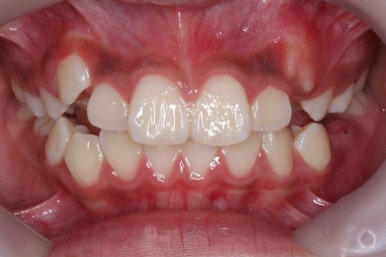

초진 시의 모습입니다.

11살의 어린이였기에 몇 군데 아직 유치가 남아있었습니다. 영구치가 모두 나오지 않았죠. 덧니가 있고 치열이 고르지 못하더라도 일반적으로 영구치가 더 나온 후에 연산동덧니교정 하는 것을 권해드립니다.

해당 환자분은 영구치가 아직 모두 나오지 않았지만 서둘려 교정을 시작한 이유는 2급 부정교합에 약간 가까웠기 때문입니다.